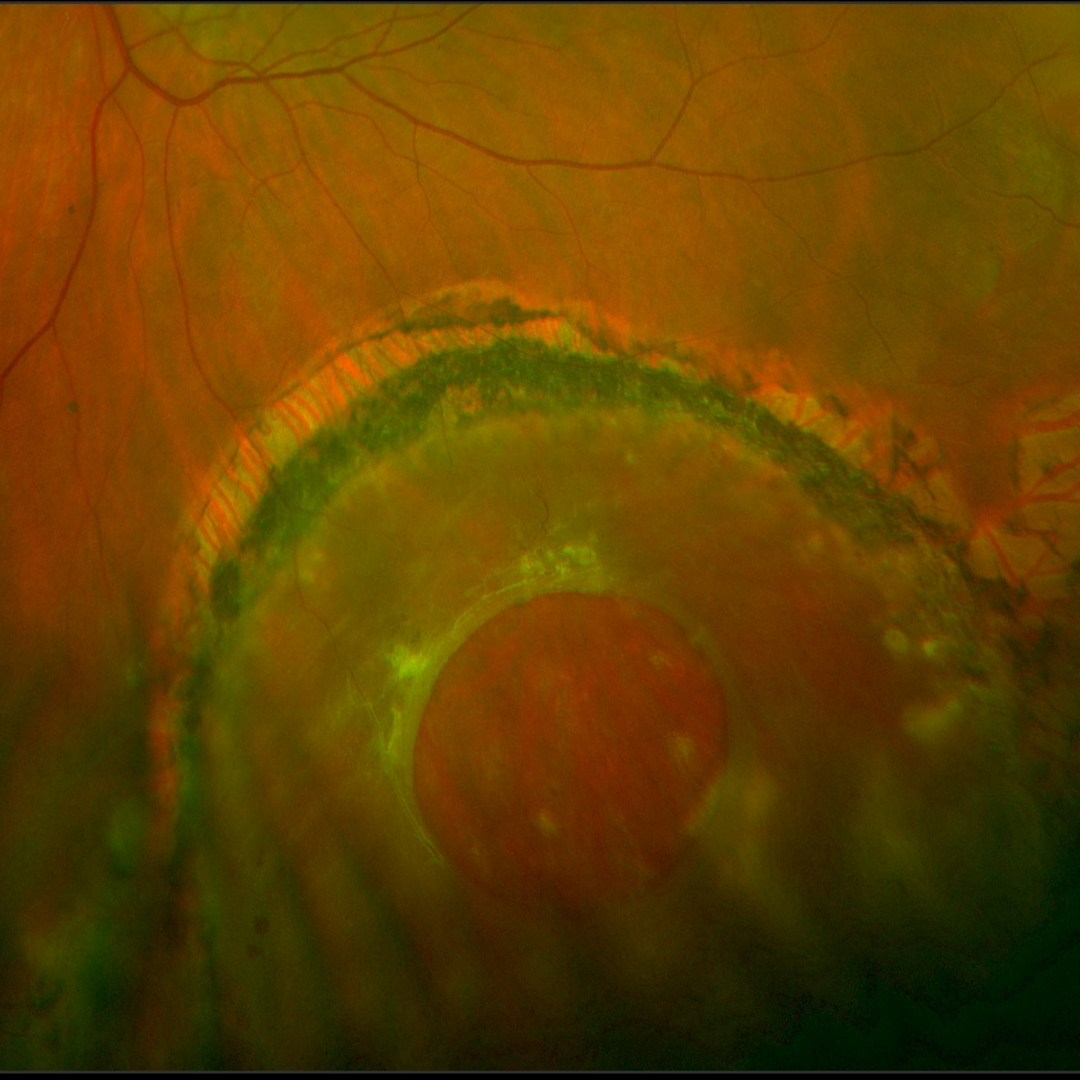

• Case 3: Macula-off detachment

A 48-year-old South American female presented with a 2-month history flashes and floaters with a subsequent black patch in her vision from her left eye. She has a history of amblyopia in that eye but notes that her vision is significantly worse than before.

Pinhole acuity in the left eye was 6/120 (20/400-) and the left pupil was found to be unreactive.

Given the clinical appearance and ocular history, this patient was referred to an ophthalmologist for reattachment surgery.

Optomap pseudocolour (top) and green separation (bottom) images - left eye

More info